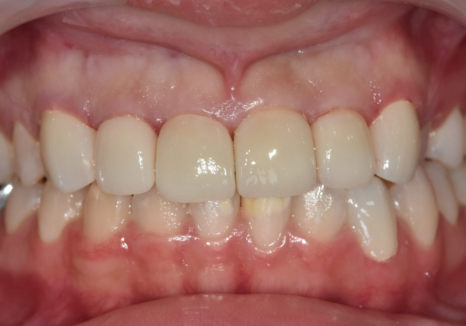

이번 환자분은 10대였고,

위 앞니 전반에 하얀 반점이

비교적 넓게 퍼져 있었습니다.

일부 치아는 반점이

치아 면적의 절반 이상을 차지해

앞니 톤이 균일하지 않은 상태였습니다.

250503 고덕역 치과 반점치 얼룩덜룩한 치아, 치료 실패 줄이는 5가지 기준

서로 다른 치료를 적용했지만,

색상과 형태는

주변 치아와 자연스럽게 어울리도록

세밀하게 조율했습니다.

250514

그 결과,

서로 다른 재료를 사용했음에도

앞니 전체가 하나의 치아처럼

자연스럽게 이어질 수 있었습니다.